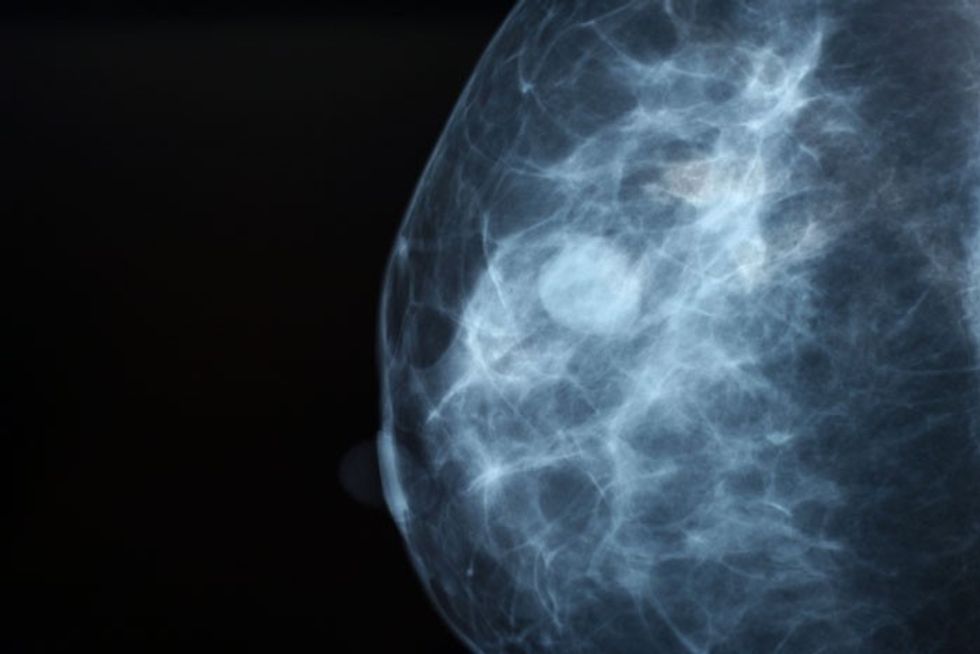

Të dhënat tregojnë se shumë prej nesh nuk kontrollohen për mutacionet që mund të çojnë në kancer të vezoreve ose kancer gjiri, të cilat e çuan Jolien drejt vendimit për të bërë një ndërhyrje kaq invazive. Kur mësojmë për eksperiencën e një të famshmi me një sëmundje, krijohet një efekt i njohur tashmë “efekti VIP”. Mirëpo veprimet tona duhet të ndërmerren në kontekstin e risqeve shëndetësore individuale. Fjalët e saj e përmbledhin shkurt mesazhin: “Kërkoni këshilla, mësoni rreth mundësive dhe bëni zgjedhjet e duhura për ju”.

“... Jolie bëri një punë të përgjegjshme”, thotë Lisa Schwartz, e cila ka studiuar efektin e mesazheve të njerëzve të famshëm me kancer te kontrolli i njerëzve të thjeshtë. Në këtë pikë, Jolie e luajti shumë mirë rolin. Nga ana tjetër, vendimi i saj për të bërë salfino-oforektomi (termi teknik për heqjen e tubave falopianë dhe vezoreve) lidhej me historinë e saj mjekësore. Kanceri ishte pjesë e historisë së saj familjare (nëna, gjyshja dhe tezja e saj vdiqën nga kanceri), por nga ana tjetër, ajo është mbartëse e një mutacioni në gjenin BRCA1.

Kontrolli i sëmundjeve shpesh shihet si mënyrë fuqizimi dhe mjet për një vendimmarrje më të mirë. Gratë si Angelina, me të afërm me kancer, janë kandidatet më të prirura për një kontroll të tillë. Mirëpo, për njerëz që nuk kanë anëtar(ë) të familjes me një sëmundje të caktuar, shpesh, kontrollet nuk ndihmojnë – që do të thotë se, kjo nuk i pakëson gjasat për të vdekur nga një sëmundje. Në fakt, kontrolli mund të shkaktojë dëme serioze – p.sh. ankth madhor, i cili, nga ana e vet, çon në vendime të panevojshme me komplikacione potencialisht serioze.

Kur vjen puna te kontrolli, duhet vlerësuar nëse ai shërben për të zgjatur, apo jo jetën e dikujt. Ndaj, vendimet e Angelina Jolie nuk duhet të influencojnë në mënyrë "të verbër" gratë e moshës së saj, pasi ajo u bazua pikërisht në riskun vetjak.